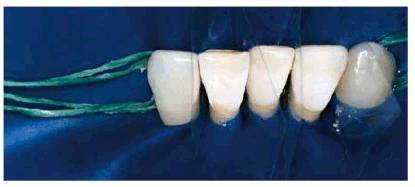

procedure can be seen in Figures 17-8A

and B 17-8C 17-8D 17-8E 17-8F 17-8G 17-8H and I, which show a 45-year-old man with

evidence of gingival and incisal abrasion, erosion, and abfraction. It is

Figure 17-8E: A rubber dam is placed, mylar strips are applied, and the teeth to be restored are etched.

Figure 17-8F: A dentin/enamel bonding agent is applied, then a dentin/enamel resin, and finally an appropriate tooth- colored microfilled composite resin is placed using a Goldstein #3 composite instrument (Hu-Friedy, Chicago, IL).